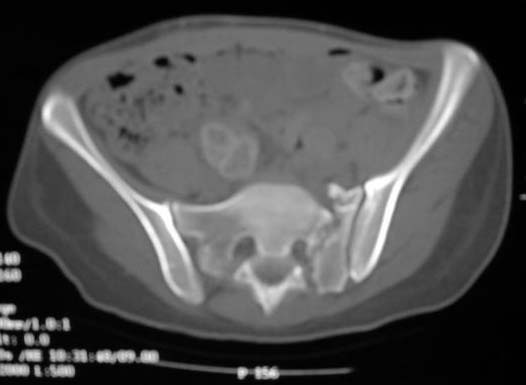

An example of our current approach to similar injuries - A 26 y.o. male admitted to us Aug 23, 2001 6 weeks after injury (compression by a wheel of a truck).

An external fixator was applied and gradual reduction was started - lateral traction to mobilize sacral fracture and then the hemipelvis was moved downward. Then lateral compression was performed. Yesterday iliosacral screws was inserted.

The last couple of images are skewed, they were made in OR and patient was not properly positioned.